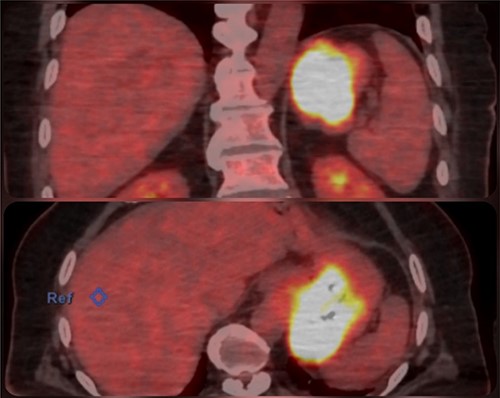

An abdominal computed tomography (CT) scan found a 9 × 8 cm subcardial lesion. The positron emission tomography (PET)-CT found a hypermetabolism on the gastric lesion with SUV max 21,5 and no locoregional hypermetabolic lymph nodes (Fig. 2).